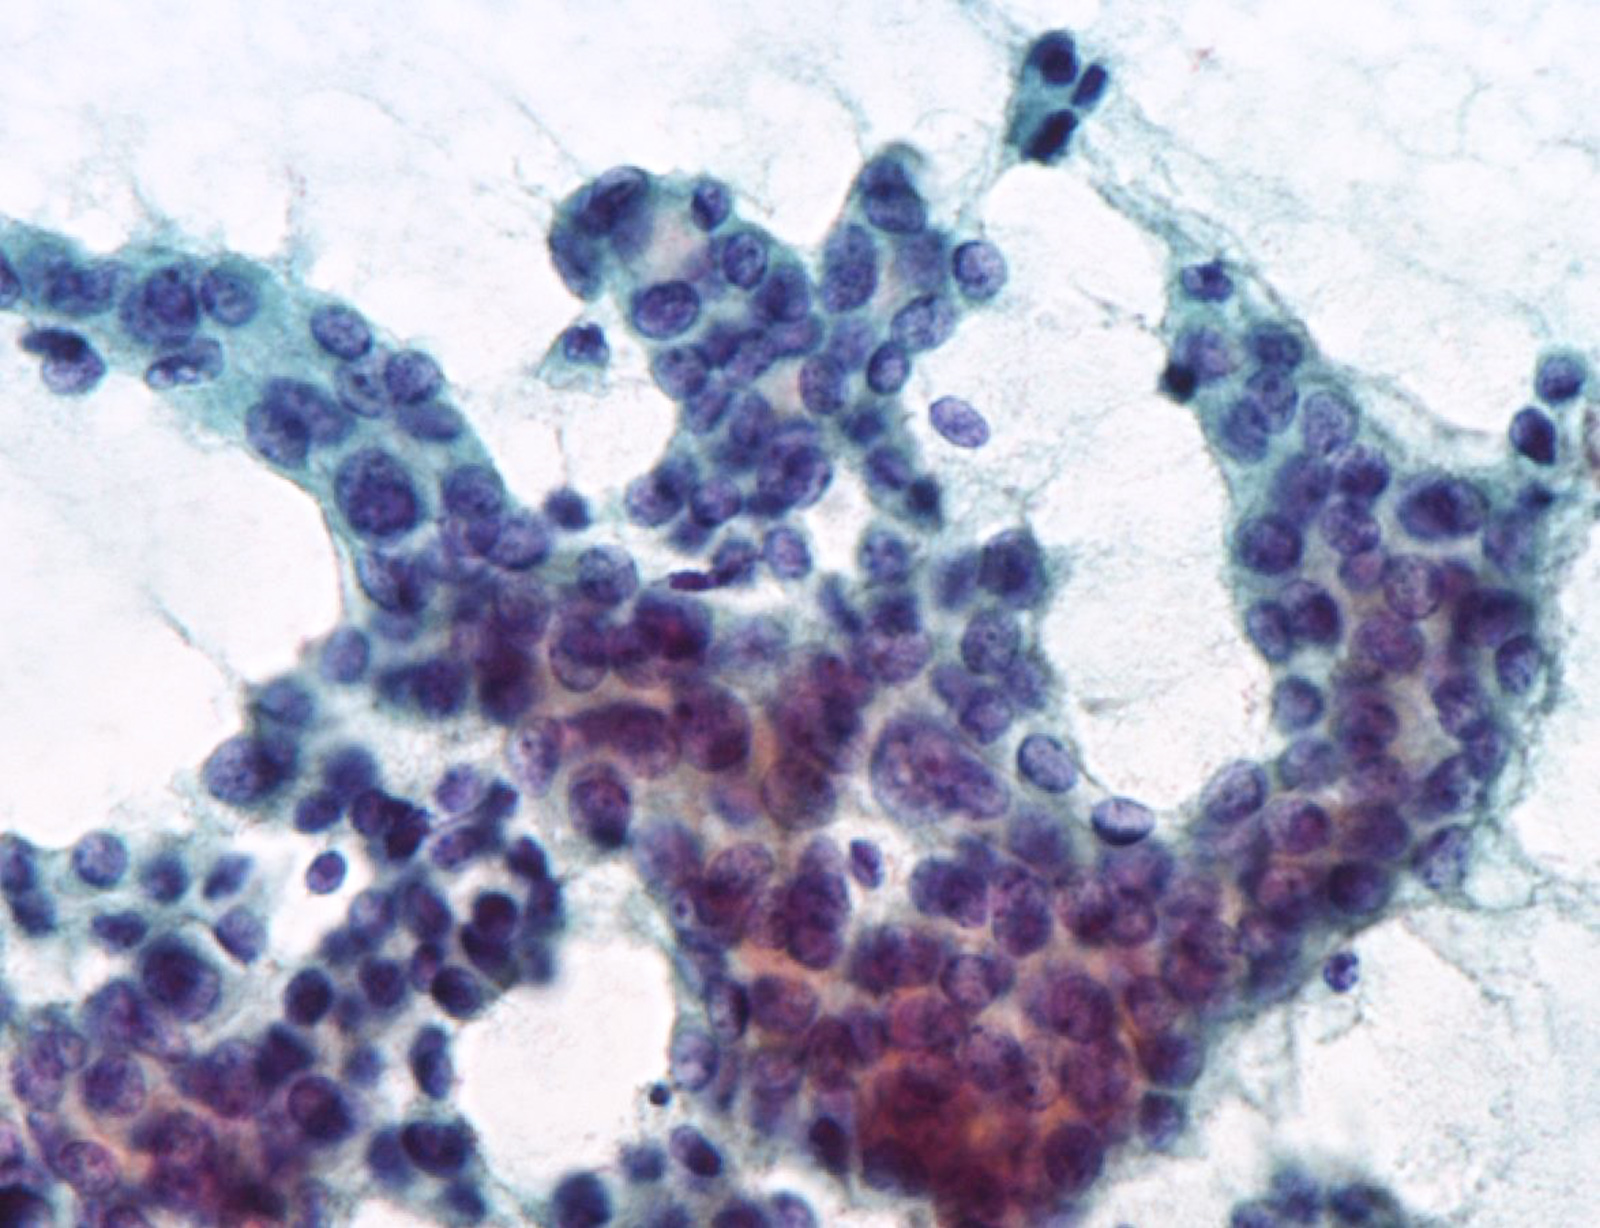

Cytology description

- Hypercellularity

- Small, round and dense colloid (hyaline colloid) may be present, sometimes within follicles

- Cells arranged in microfollicles or trabecular pattern

- Nuclear enlargement but may lack prominent nuclear features of papillary carcinoma (Am J Clin Pathol 1999;111:216)

- Highly suggestive of syncytial clusters, microfollicular architecture, chromatin clearing and nuclear grooves (Acta Cytol 2006;50:663)

- Classified by Bethesda system as categories III to VI

- Cytologically unable to distinguish between noninvasive and invasive

Cytology images

Contributed by Ayana Suzuki, C. T.